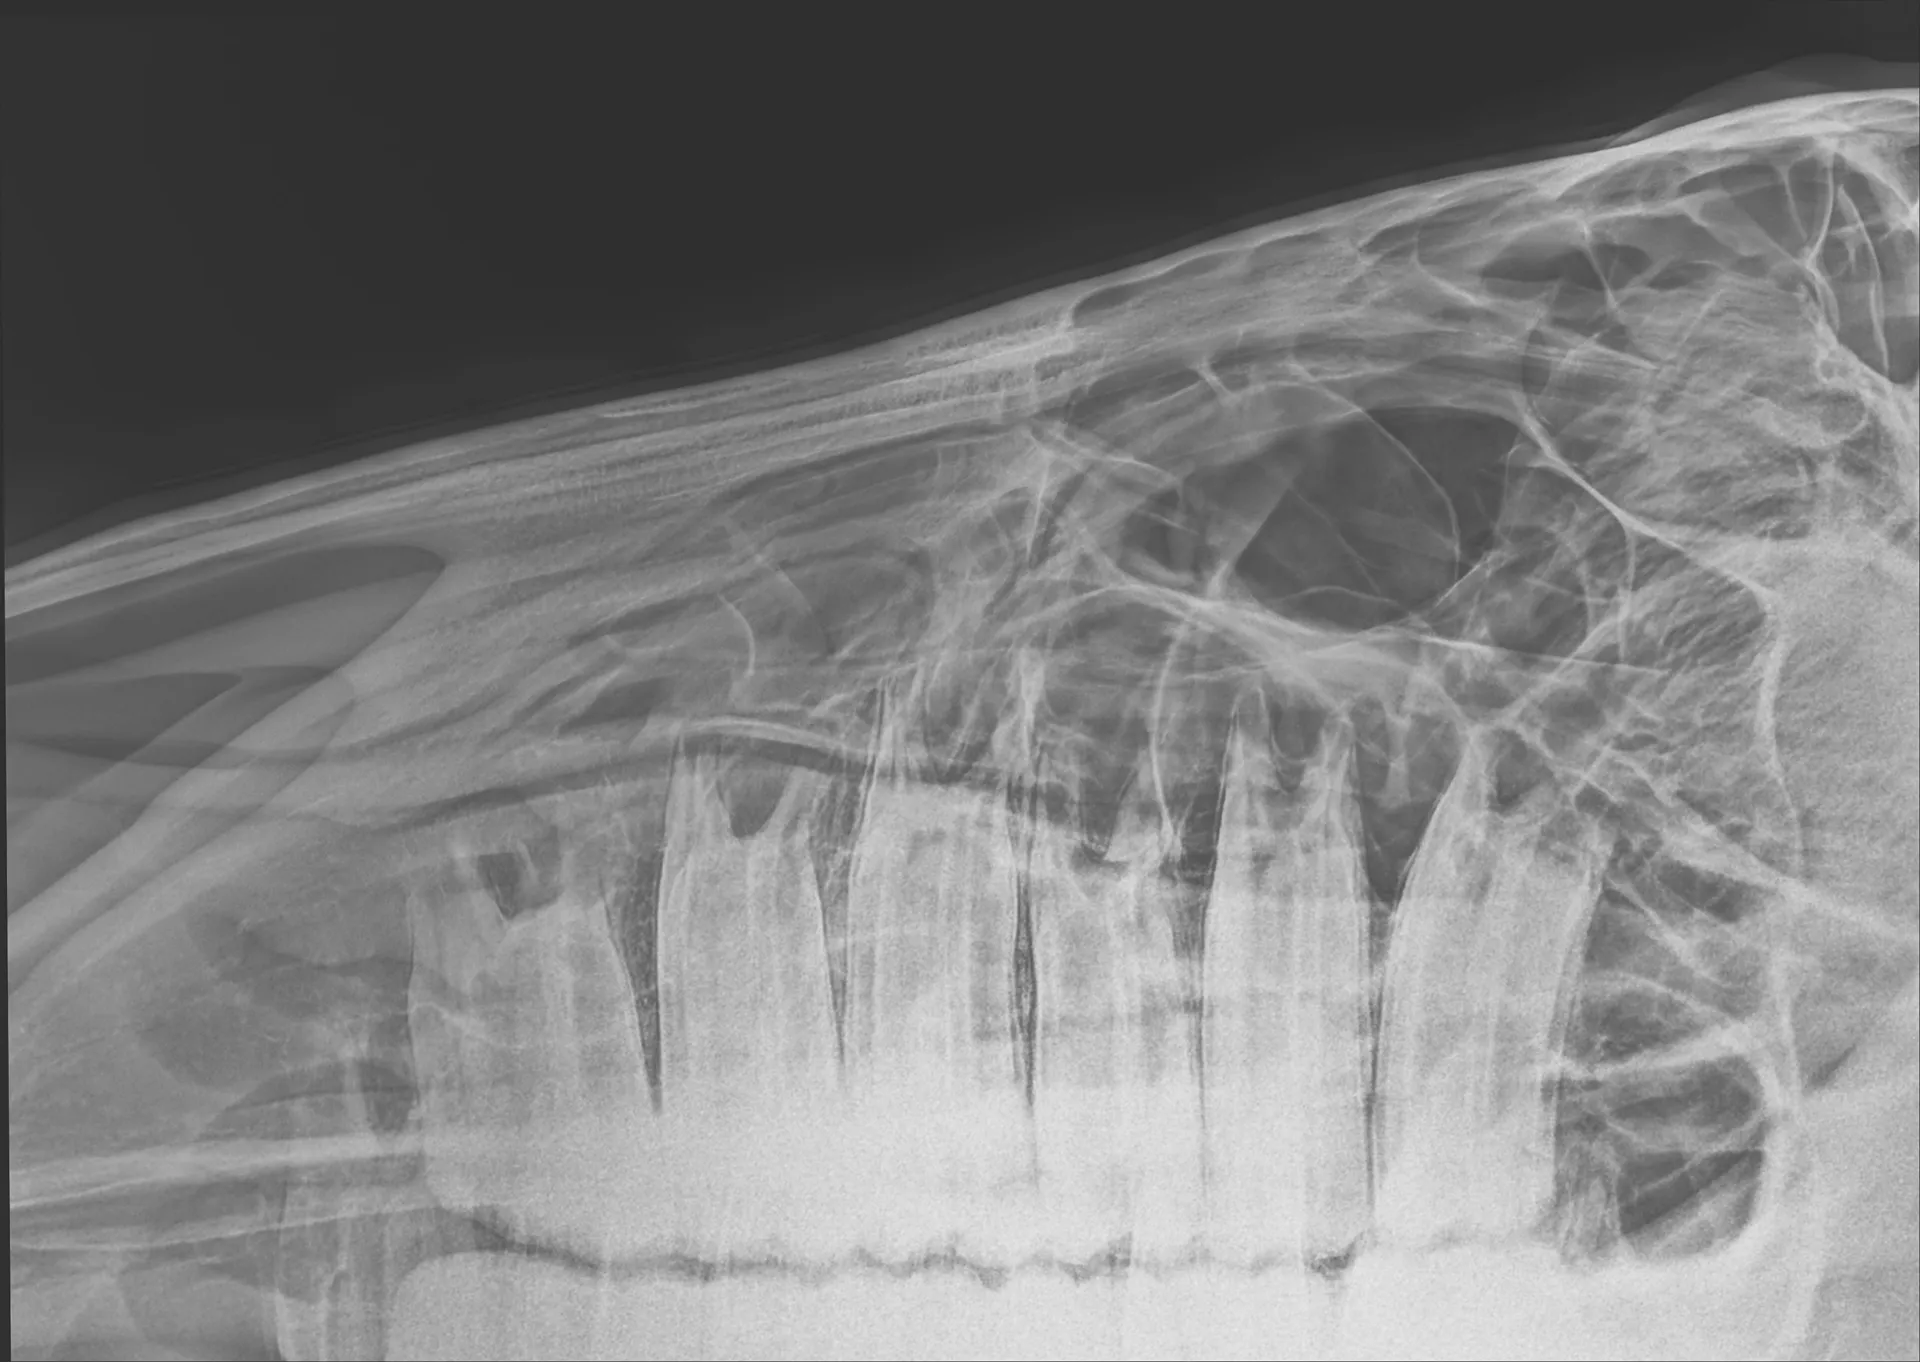

Equine Dentistry

CCEV provides both routine and advanced equine dental care, ensuring your horse’s dental health is maximised for both performance and longevity.

Regular equine dental health checks under sedation are essential for maximising dental longevity, oral health, physical condition, performance, and long-term wellbeing. We combine routine care with advanced techniques to meet the needs of every horse.

Christopher holds an advanced veterinary practice certificate in equine dentistry, which involves several years of additional training. So you can rest assured knowing your horse is in the best hands.